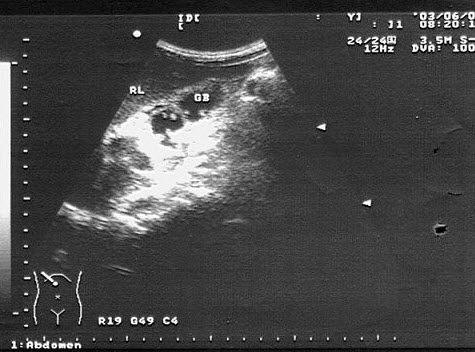

17、单项选择题

男,64岁,右上腹反复疼痛不适数10年,加重5天。声像图如图所示,诊断为()

A.肝内钙化带

B.胆囊充满型结石并萎缩性胆囊炎

C.胆囊蛔虫

D.肠襻回声

E.胆囊癌